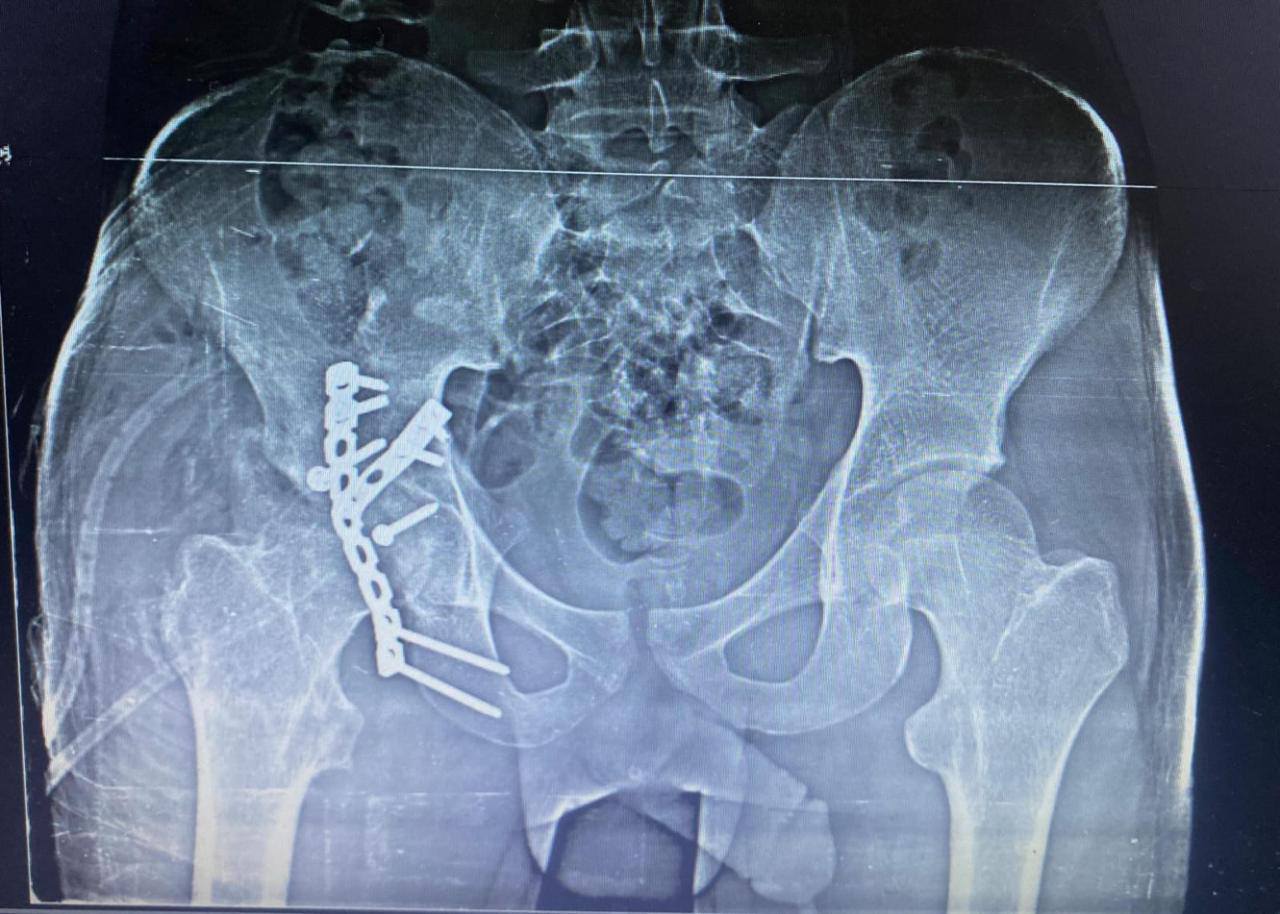

أ.د/ حسام الدين جاد – رئيس قسم جراحة العظام نجحت وحدة جراحات الحوض المتقدمة بقسم جراحة العظام والكسور في إجراء عملية معقدة لرد وتثبيت كسر مهمل بالجدار الخلفى للحق الحرقفى مع وجود خلع مهمل بالمفصل وتحرير العصب الوركى حيث انه حضر إلينا المريض يعانى من آلام فى الحوض وسقوط جزئى بالقدم بعد مرور شهرين من إصابته فى حادث وتم عمل اشعة فتبين وجود خلع مهمل مع كسر بالجدار الخلفى للحق الحرقفى بمفصل الفخذ وتم دخول الحالة للعمليات حيث تم استكشاف وتحرير العصب الوركى وعمل رد مفتوح للخلع وازالة التعظم بالانسجة المحيطة واعادة بناء الجدار الخلفى للحق باستخدام رقعة عظمية من داخل عظام الحوض وتثبيت الكسر بواسطة شرائح ومسامير وتم خروج المريض من العمليات بنجاح.